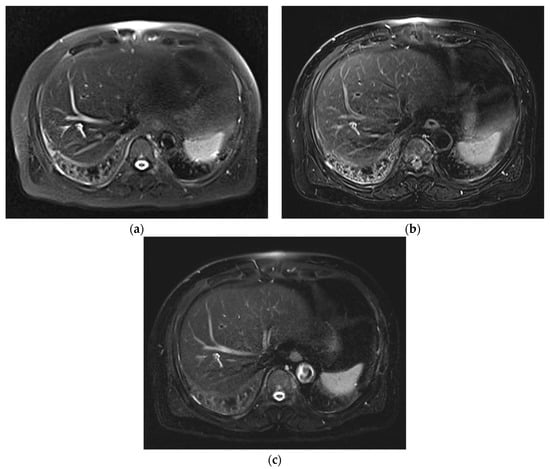

3. Results

3.1. Subjective Image Quality

3.2. Lesion Assessment